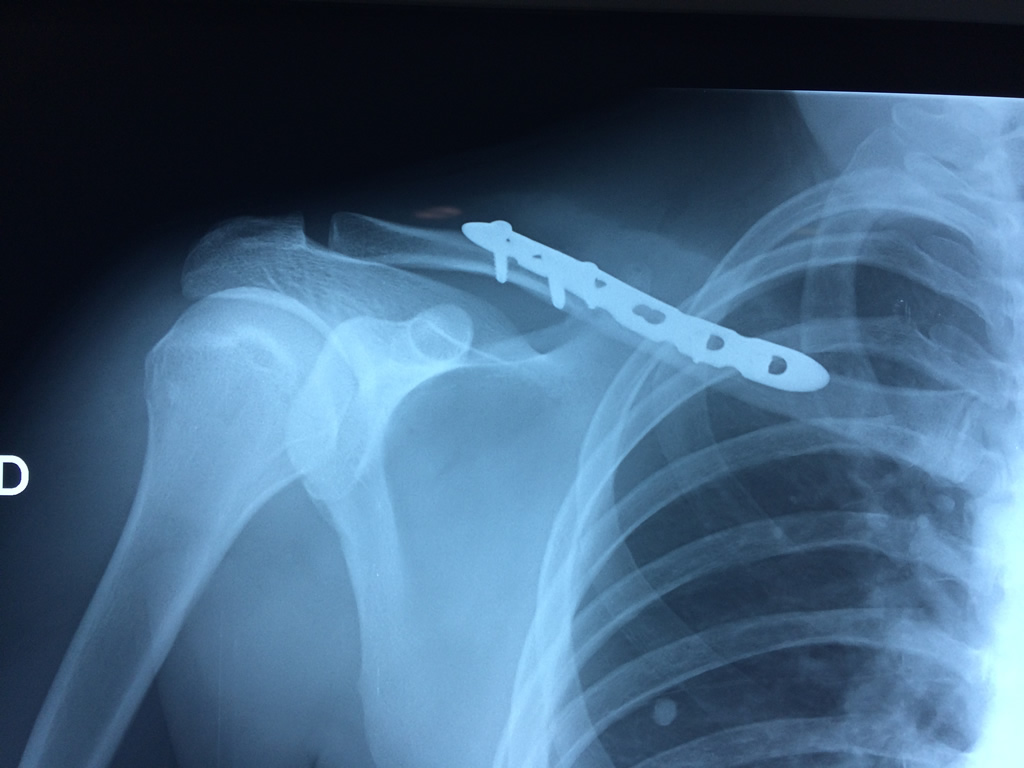

Calcaneo - Clavícula

La clavícula es un hueso largo, con forma de "S" itálica, situado en la parte anterosuperior del tórax. Junto con la escápula forman la cintura escapular. Se puede palpar por toda su longitud y se extiende del esternón al acromion de la escápula, siguiendo una dirección oblicua lateral y posterior.